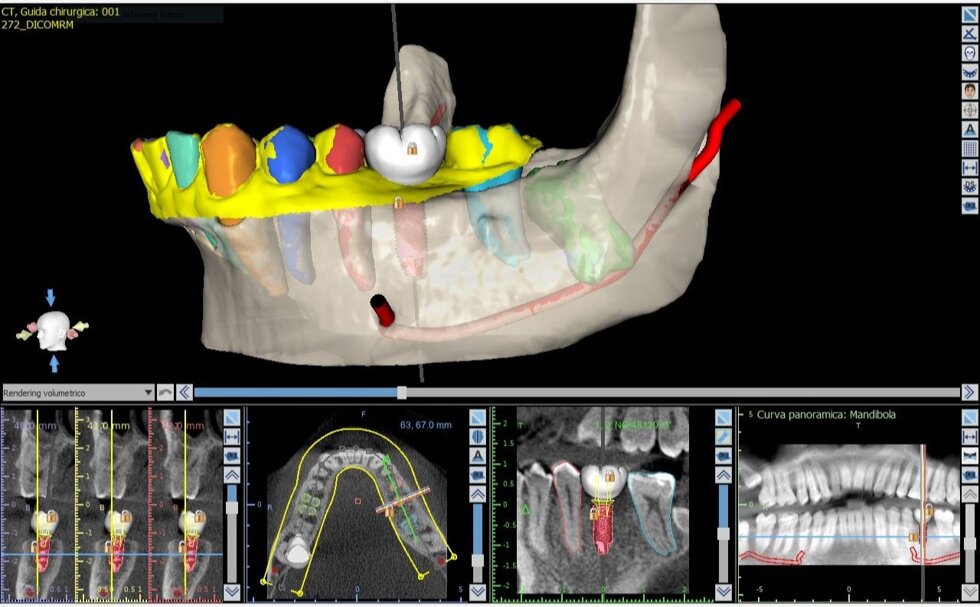

Il processo inizia con una tomografia computerizzata (CBCT), che fornisce un’immagine tridimensionale dettagliata delle arcate dentarie e delle strutture ossee. I dati vengono importati in software dedicati, dove il chirurgo può pianificare virtualmente l’intervento: scegliere la posizione, l’inclinazione e la profondità ottimali di ciascun impianto, valutando anche la densità ossea e la distanza da nervi o seni mascellari.

Una volta definito il piano chirurgico, si procede alla realizzazione di una dima chirurgica personalizzata, ottenuta tramite stampa 3D. Questa mascherina guida gli strumenti del chirurgo durante l’intervento, consentendo di inserire gli impianti nella posizione esatta prevista dal progetto digitale, senza necessità di ampie incisioni gengivali.